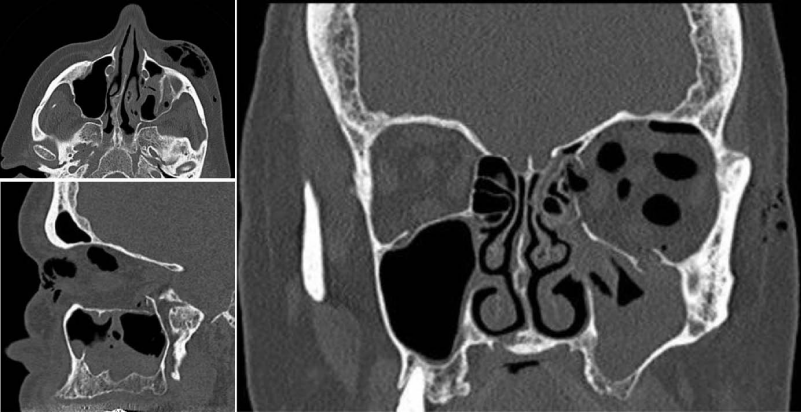

Isolated blow-out-fractures of the orbital floor especially in elderly people rarely lead to subsidence of the corresponding eye-bulb. Mostly a high-stand of the bulb was diagnosed by the ophthalmologist owed to intraorbital emphysema and haematoma. The eye-bulb and eye-muscles are protected by the periorbital fat-tissue and even in case of a prolapse of a small part of the periorbital fat-tissue no entrapment of the caudal muscels occurs in almost all cases. Furthermore a clear distinction between haematoma and periorbital fat-tissue cannot be made in most CAT-scan-investigations and mostly the bulb and periorbital tissue are statical and functional stabilized by the intact surrounding orbital floor (Figure 8). Contrary, a surgical reduction of the fractured orbital floor seems to lead to a significant prolonged diplopia compared to the patient-group without surgical intervention as the results of this study suggest (Table 8).

Figure 8:

CAT-scan series from frontal to dorsal through an isolated fracture of the orbital floor. Haematoma cannot be distinguished from periorbital fat-tissue and unity of bulb, muscels and periorbital tissue are stabilized by anterior, posterior, central and lateral intact parts of the orbital floor. No diplopia was diagnosed in this case and no restriction in eye-movement.